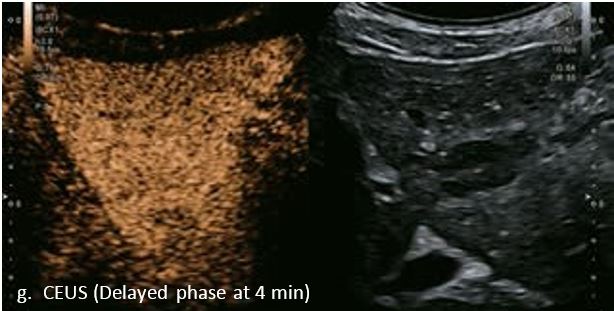

LI-RADS 4 множинні ГЦК

Це випадок 60-річної жінки з декомпенсованим цирозом печінки з асцитом. На сірошкальному зображенні можна виявити два вогнищевих ураження, розміром 21 мм і 10 мм відповідно, розташовані в сегменті 5. Оскільки дослідження методом зсувної хвилі на апараті Canon виконується штовхаючим імпульсом, пацієнтам з асцитом не можна проводити дослідження за допомогою зсувної хвилі, для визначення стадії фіброзу. На ранній артеріальній стадії гомогенне гіперехогенне підсилення спостерігається в обох ураженнях. Ураження є ізоехогенними в портальній венозній та пізній фазах, вимивання не спостерігається через 6 хвилин після ін'єкції, тому ці ураження були класифіковані як LI-RADS 4, ймовірна ГЦК. Важливо знати, що LI-RADS 5 - це ГЦК зі 100% вірогідністю, і вона не потребує біопсії. Значна кількість LI-RADS M (ймовірно або точно злоякісні, але не специфічні для ГЦК) і LI-RADS 4 (ймовірна ГЦК) насправді являються ГЦК.

Малюнок 11